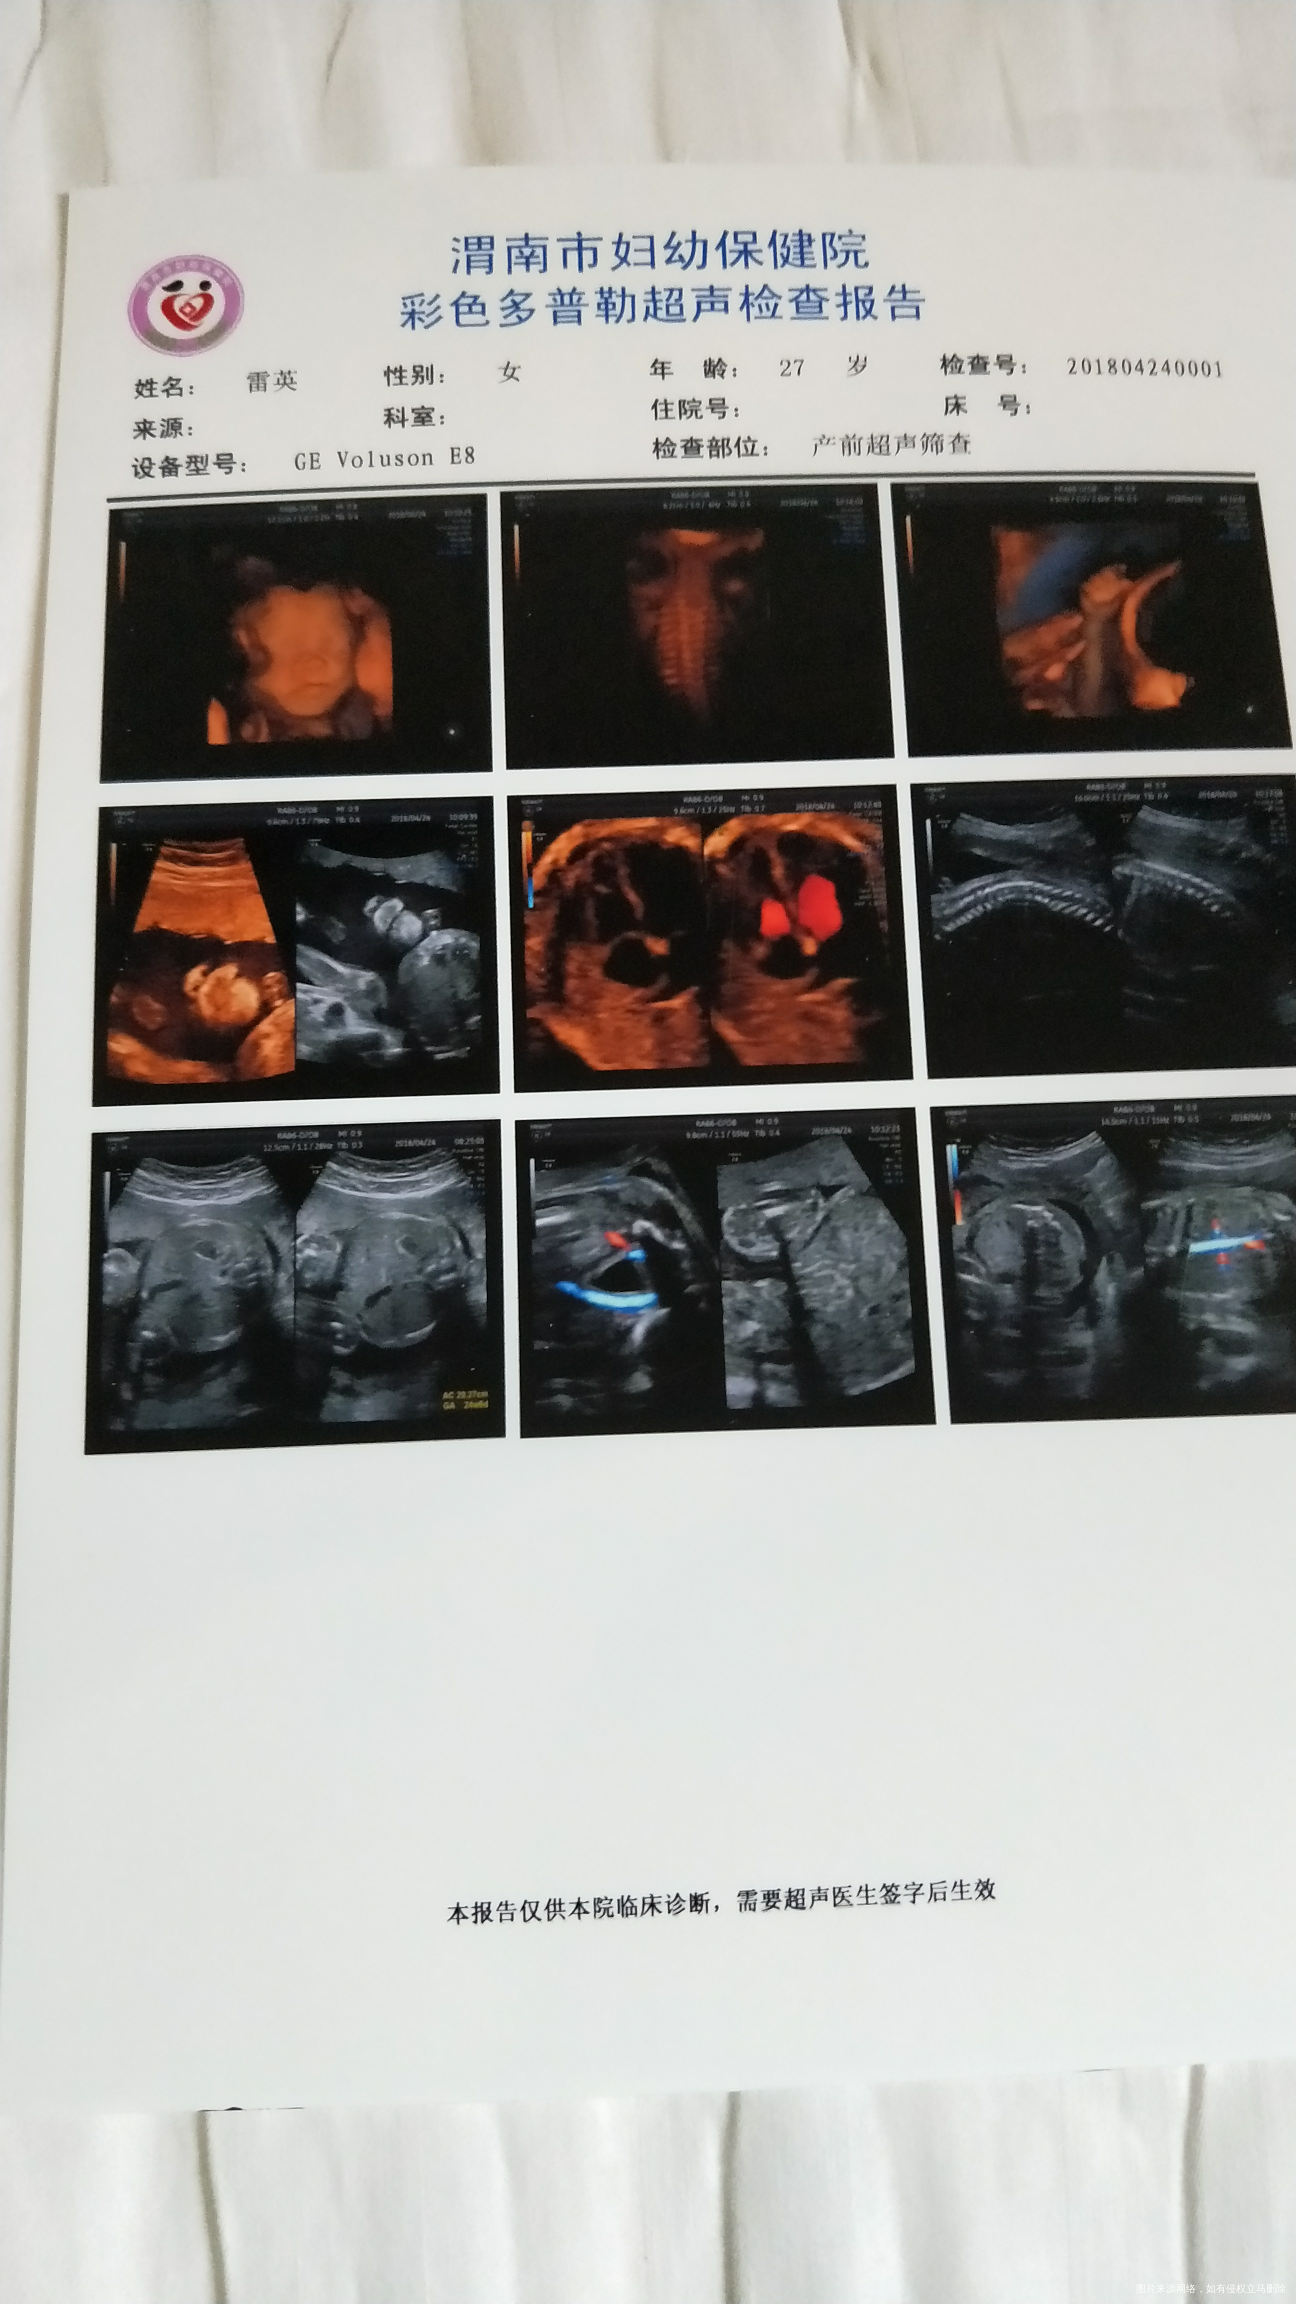

试管婴儿怀孕24周加1天,四维b超胎儿有心包积液怎么办?脐带绕颈一周

您好,各种原因的胎儿水肿都可以表现为胎儿心包积液,而导致胎儿水肿的原因多与胎儿、脐带、羊水等因素有关,胎儿因素可见于母儿血型不合、胎儿畸形等。意见建议:建议您28周复查彩超,32周再复查,如果积液量越来越小,可以不必担心,祝好孕!